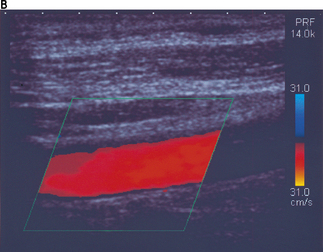

Figure 11.15a illustrates color aliasing which is caused when the color scale is set too low. The Doppler signals are undersampled at a PRF = 12.5 kHz which corresponds to a maximum color scale velocity of 13.9 cm/s. In this example, color flow changes from BLUE to RED are observed within the vessel. Increasing the color scale increases the PRF, from 12.5 kHz to 14 kHz, which is sufficient enough to eliminate aliasing within the image, as demonstrated in Figure 11.15b.

image image

Fig. 11.15 a) The color scale is set too low, resulting in aliasing of the color Doppler signal. The Doppler signals are undersampled at a PRF = 12.5 kHz. b) The color scale and PRF are increased to ensure that the Doppler signals are adequately sampled, resulting in the elimination of aliasing. This is achieved at a higher PRF of 14 kHz